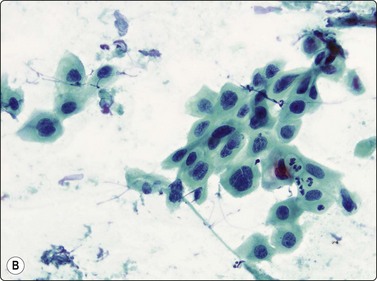

Fig. 8.1 Bronchiolar epithelium

Small sheet of regular glandular cells (Pap, HP).

Bronchial epithelium may be abundant in percutaneous FNB if the needle traverses a medium-sized bronchus or tracks along a bronchial lumen. Transbronchial FNB may also yield abundant bronchial epithelium. Bronchial epithelium appears as small palisaded clusters with a ciliated border. In large aggregates the cells may present as flat sheets with a pavement-like aspect, but ciliated cells can usually be observed at the edges of these sheets.

Bronchiolar epithelium or nonciliated epithelium is seen commonly as sheets of various size (Fig. 8.1). They usually have irregular edges and the component cells display variable cell separation. The nuclei are generally small and there is a low nuclear:cytoplasmic (N:C) ratio. Sometimes the nuclear outlines are slightly irregular and small intranuclear cytoplasmic inclusions are observed. Occasionally, atypia of bronchiolar epithelium may be quite pronounced, for example in reactive or inflammatory processes; however, the number of atypical cells is usually small. A diagnosis of malignancy should generally not be made on the basis of small numbers of cells.